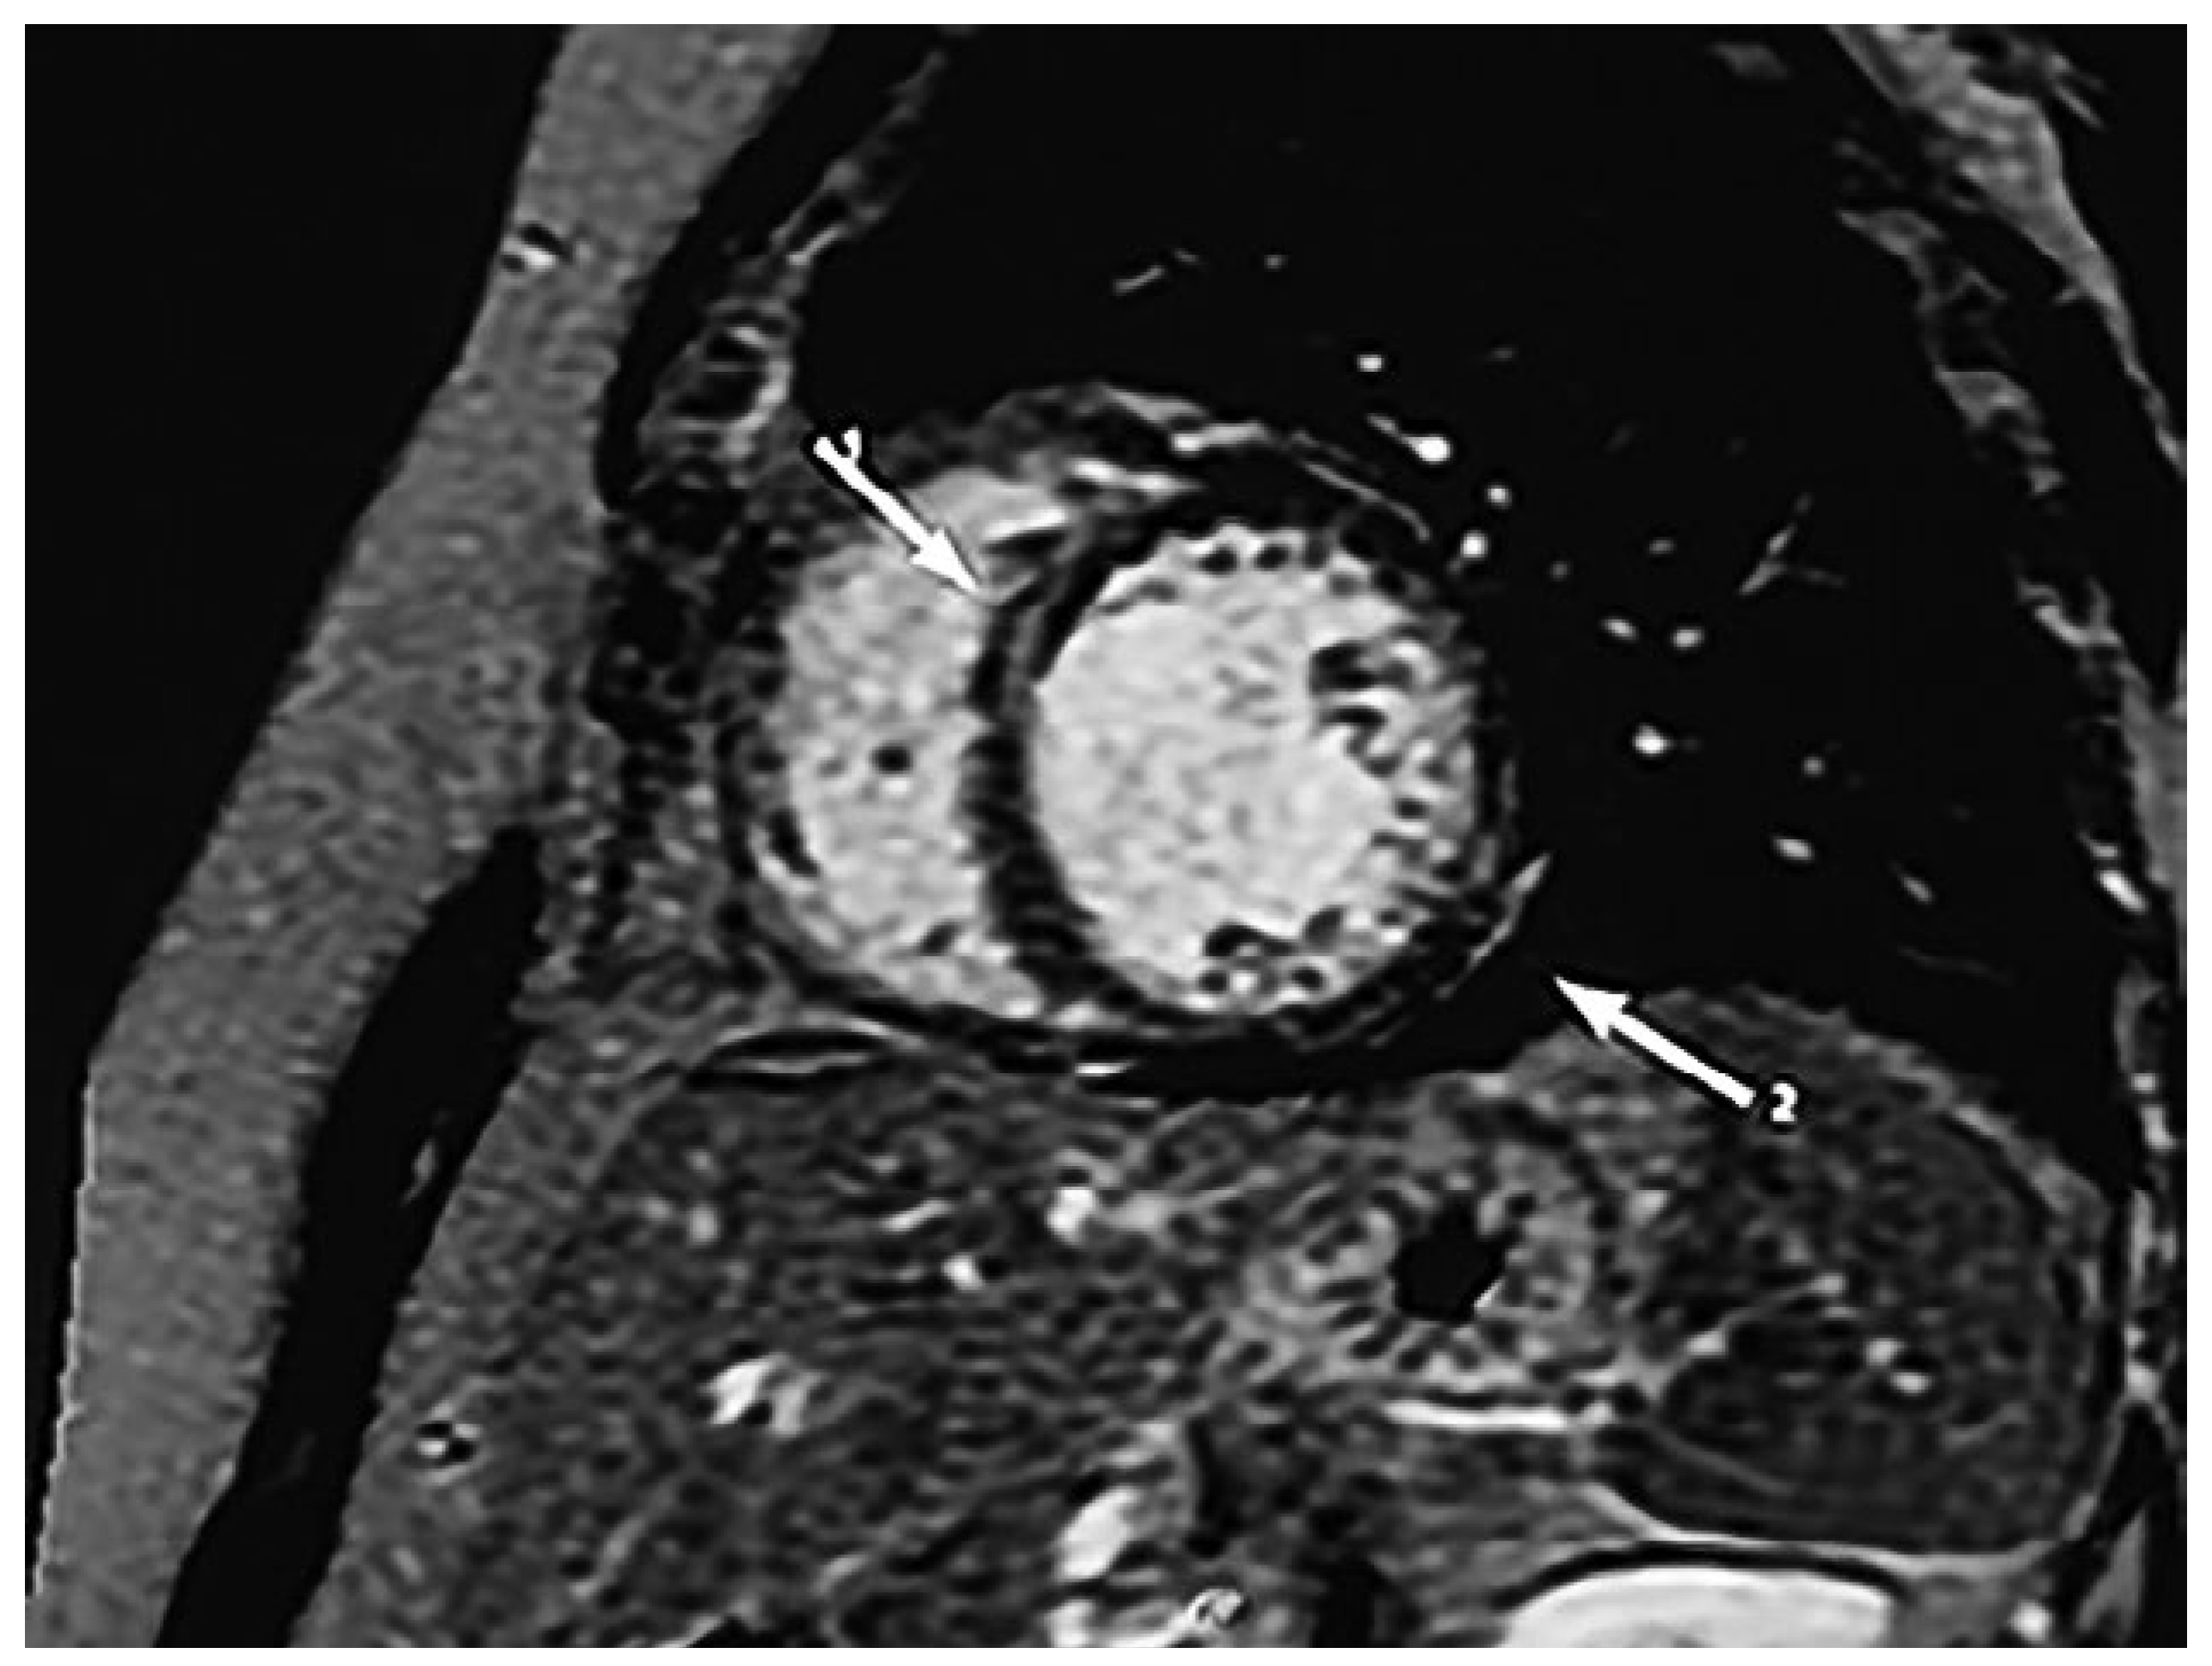

Subsequent cardiac magnetic resonance imaging (CMR) showed a dilated left ventricle with diffuse hypokinesia, but an already improved EF of 40%. There was no oedema within the myocardium, but late gadolinium enhancement was present in the septum and the lateral epicardial wall (Figure 1).

Figure 1.

CMR with late gadolinium enhancement in the septum (1) and lateral wall epicardially (2) (marked by arrows).

According to the current European Association of Cardiovascular Imaging (EACVI) expert consensus from 2017, echocardiography may demonstrate diastolic dysfunction in early cardiac stages. Segmental left ventricular wall motion abnormalities may be present, more frequently in the inferior and inferolateral walls and the apex region. This may range from mild wall motion abnormalities to aneurysm formation. Apical aneurysm is typical in Chagas disease, but localisation is not limited to the apex alone. However, our patient did not show any aneurysm formation. In cases of unsatisfactory echo quality, application of contrast echocardiography or additional CMR is highly recommended by the current consensus of experts, as it may better demonstrate the wall motion abnormities and LVEF [6]. CMR should also be considered to quantify the extent of myocardial fibrosis through late gadolinium enhancement. Late gadolinium enhancement is heterogeneous in Chagas cardiomyopathy, sometimes even located epicardially, making ablation treatment of arrhythmias such ventricular tachycardia by technically challenging.